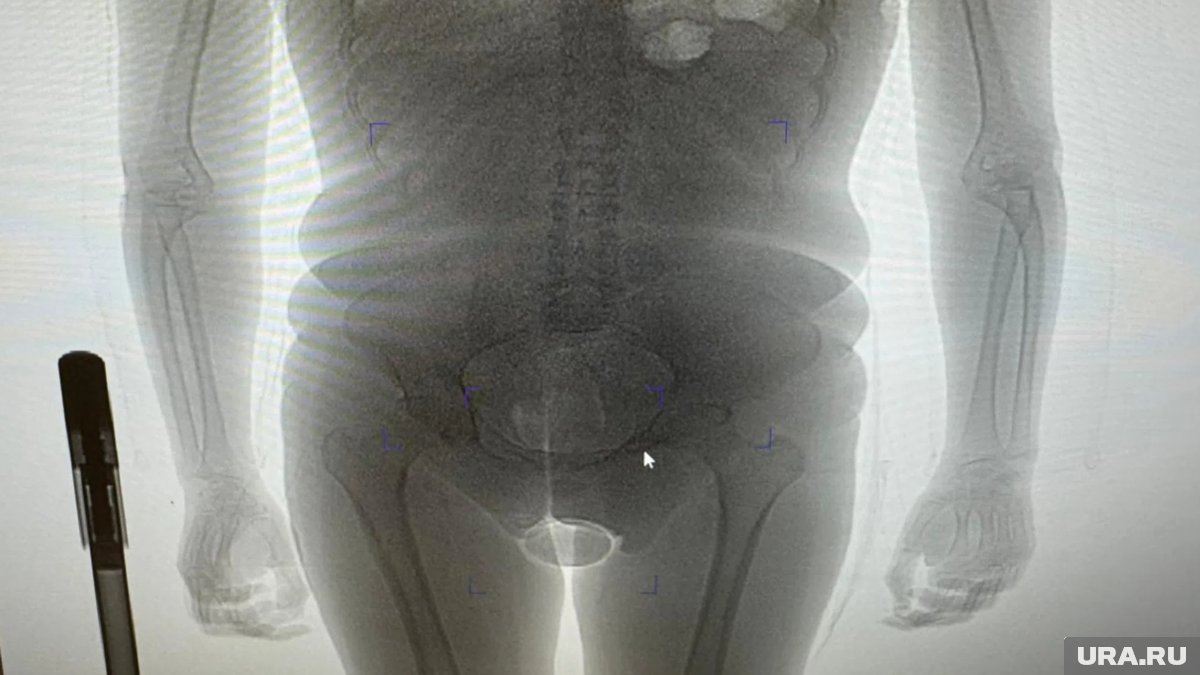

Сотрудники таможенного поста аэропорта Домодедово задержали гражданку Бразилии, подозреваемую в попытке незаконного ввоза наркотиков внутриполостным способом. По данным ведомства, 22-летняя пассажирка, прибывшая рейсом из Дубая, была остановлена в «зеленом» коридоре в рамках проведения оперативно-разыскных мероприятий. Об этом для URA.RU сообщила пресс-секретарь Домодедовской таможни Елена Мартынова.

«В результате проведения таможенного досмотра обнаружено два презерватива с порошкообразным веществом внутри, один из которых находился в нижнем белье пассажирки, второй сокрыт внутриполостным способом», — говорится в заявлении пресс-секретаря. Информация есть в распоряжении URA.RU.